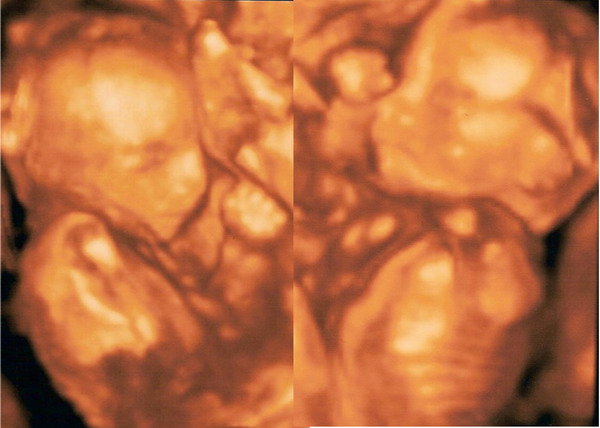

megkérdezhetem hogy melyik a kisfiú és melyik a kislány?

olyan édesek, gratula hozzájuk

A bal oldali a kislány a jobb oldali a kisfiú. :)